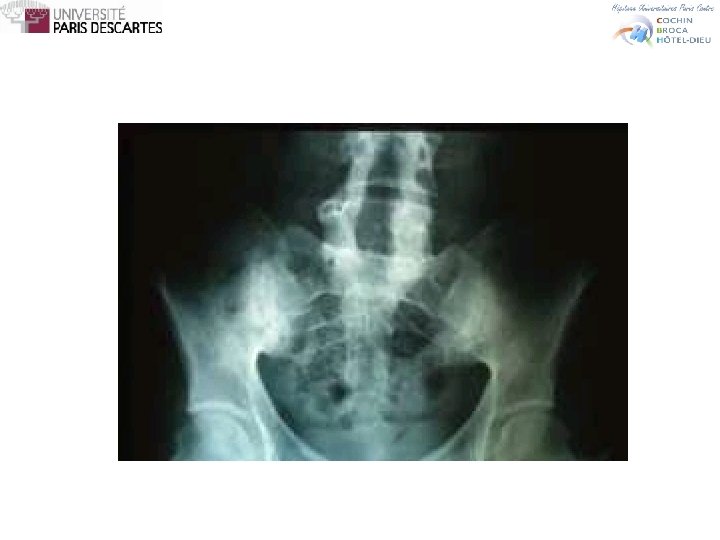

SPONDYLARTHROPATHIES Diagnostic • Lombalgie ≥ 3 mois • Ayant débuté avant 45 ans Sacroiliite +1 signe ou HLA B 27 +2 signes • Lombalgie inflammatoire • Synovite • Enthésite (talalgie) • Uvéite • Dactylite • Psoriasis, entérocolite • Réponse aux AINS • Histoire familiale de Sp. A • HLA B 27 • CRP augmentée

SPONDYLARTHROPATHIES Exemple • Lombalgie chronique inflammatoire • RN, RM • Efficacité des AINS • Uvéite • Psoriasis • Entérocolite • Synovite • Enthésite • CRP • Rx bassin • IRM